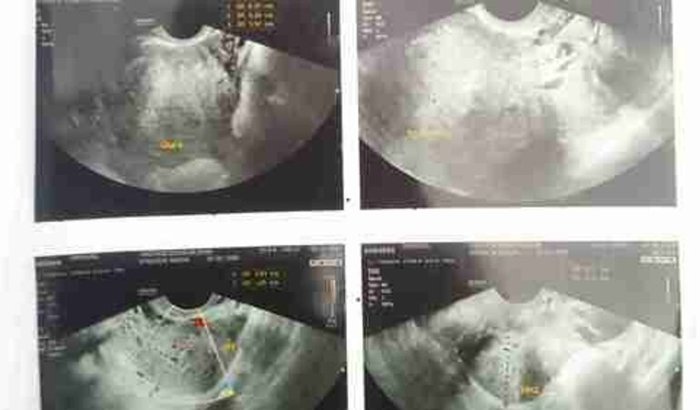

Eu me chamo Josefa criei essa vaquinha para arrecadar no máximo 8.000 para fazer minha cirurgia estou com sangramento muito forte e sentindo muita dor com três miomas ver tudo

Eu me chamo Josefa criei essa vaquinha para arrecadar no máximo 8.000 para fazer minha cirurgia estou com sangramento muito forte e sentindo muita dor com três miomas